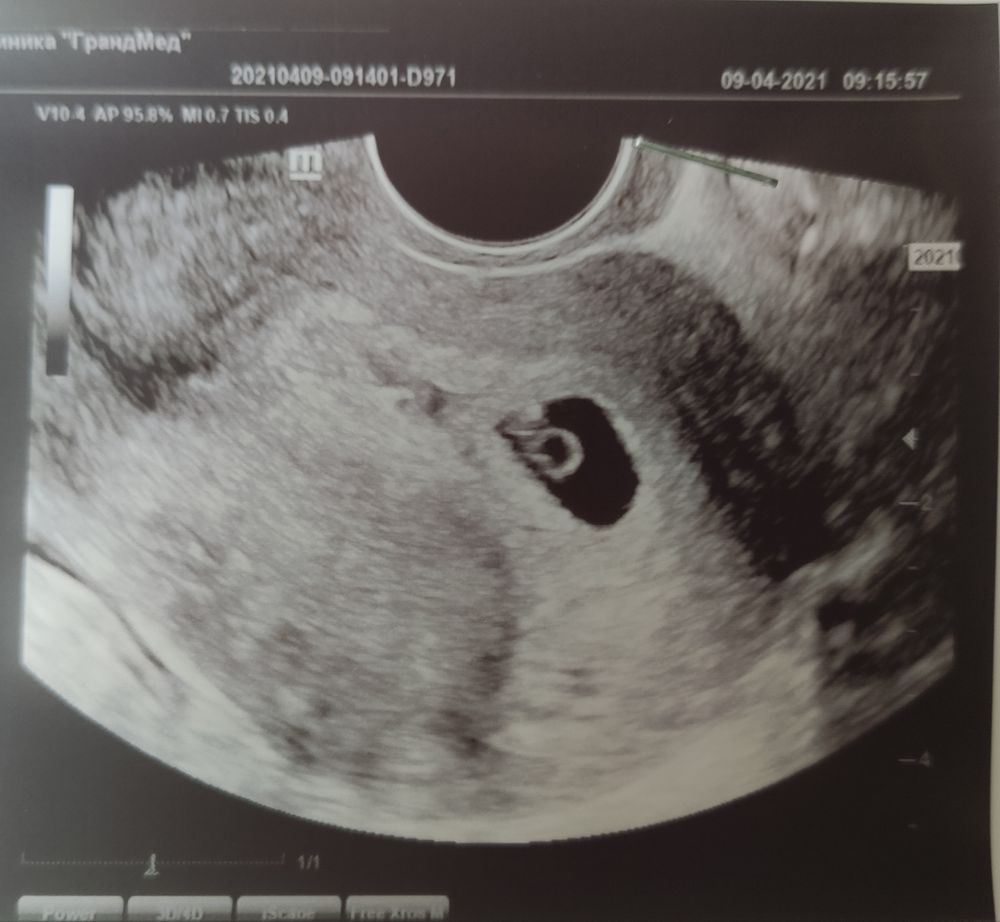

УЗИ 6 недель

ЧУДЕСА СЛУЧАЮТСЯ! Я БЕРЕМЕННА!Сегодня ровно 6 недель акушерских, была на УЗИ у репродуктолога, который проводил стимуляцию овуляции.

Подтвердили беременность 😍. Сроки по УЗИ совпадают, сердечко бьётся! Божечки, это что-то за гранью реального.. видеть, как у такого маленького существа бьётся сердце 💓